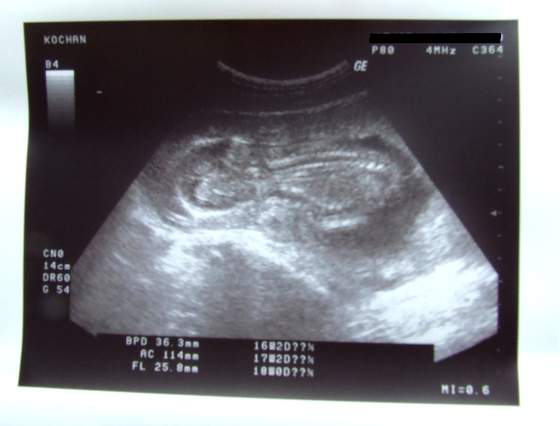

Joasia tyle dzis trzymało nas kciukasy,że musialobyc wszystko w porządkuciesze sie ,ze z dzidza okej, oby juz same dobre wiesci z wizyt były

![]()